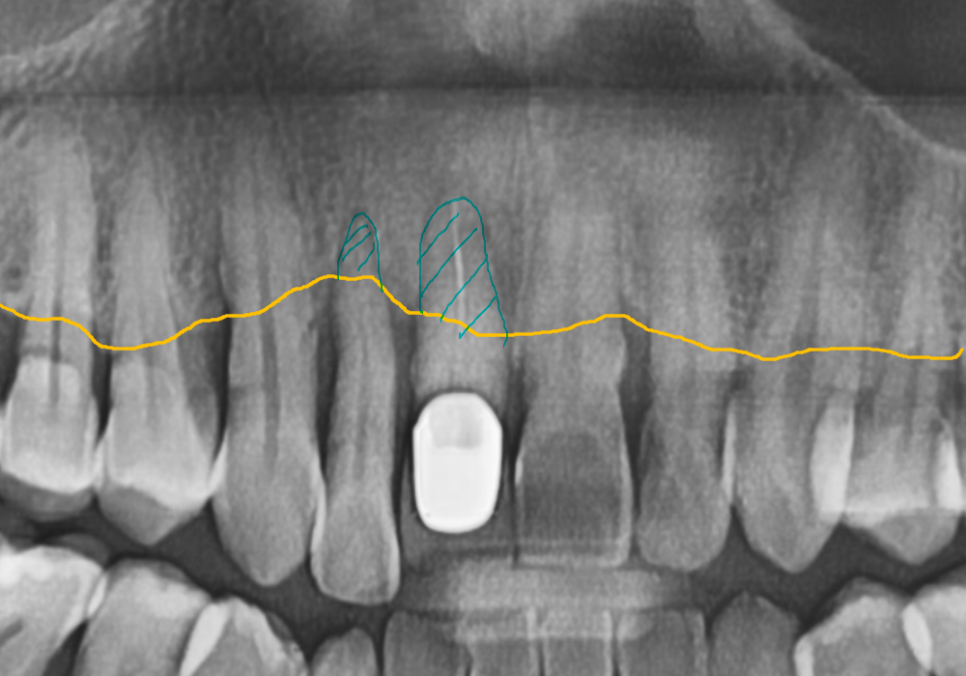

CT 분석 결과 중앙 앞니(#11) 치아 뿌리 끝에

염증이 발견되었지만,

환자분께서 최대한 자기 치아를

더 써보고 싶어 하셔서

일단 흔들림이 심한 오른쪽 앞니(#12)만

발치하고 임플란트를 진행했습니다.

C뿌리 끝 염증도 더 심해진 상황...

251125

안타깝지만 이 치아도 발치 후

임플란트로 재건하기로 결정했습니다.